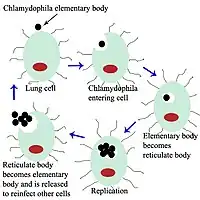

Chlamydia psittaci is a small bacterium (0.5μm) that undergoes several transformations during its lifecycle. It exists as an elementary body (EB) between hosts. The EB is not biologically active, but is resistant to environmental stresses and can survive outside a host. The EB travels from an infected bird to the lungs of an uninfected bird or person in small droplets, and is responsible for infection. Once in the lungs, the EB is taken up by cells in a pouch called an endosome by phagocytosis. However, the EB is not destroyed by fusion with lysosomes, as is typical for phagocytosed material. Instead, it transforms into a reticulate body and begins to replicate within the endosome. The reticulate bodies must use some of the host's cellular machinery to complete their replication. The reticulate bodies then convert back to elementary bodies, and are released back into the lung, often after causing the death of the host cell. The EBs are thereafter able to infect new cells, either in the same organism or in a new host. Thus, the lifecycle of C. psittaci is divided between the elementary body which is able to infect new hosts, but can not replicate, and the reticulate body, which replicates, but is not able to cause new infection.